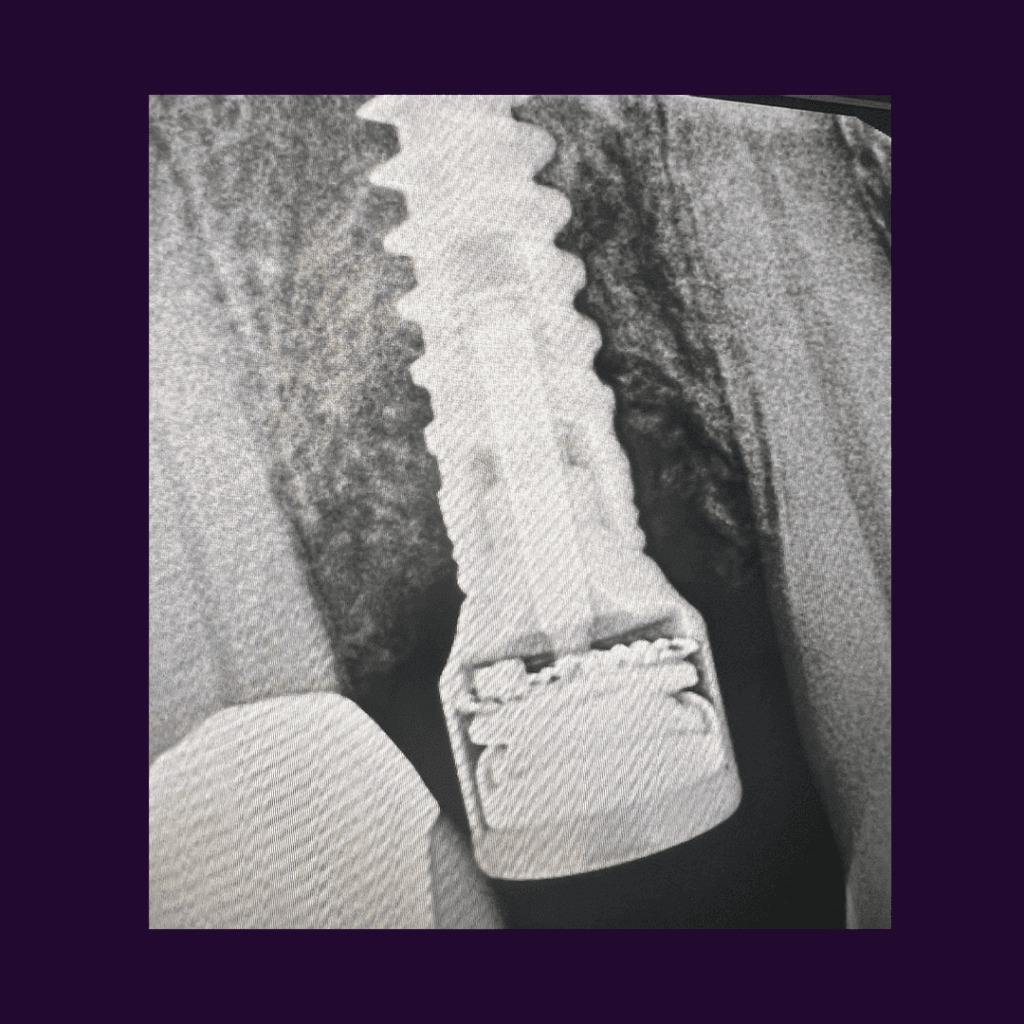

Peri-Implantitis: A Growing Concern in Dental Implantology

Peri-Implantitis: A Growing Concern in Dental Implantology Peri-implantitis is an inflammatory condition that affects the tissues surrounding a dental implant, leading to the progressive loss of supporting bone. This condition is becoming increasingl

The Role of Pulsed Electromagnetic Fields in Managing Peri-Implant Conditions

The Role of Pulsed Electromagnetic Fields in Managing Peri-Implant Conditions Pulsed Electromagnetic Field (PEMF) therapy is gaining attention as a non-invasive treatment option for managing peri-implant conditions, including peri-implantitis. This i